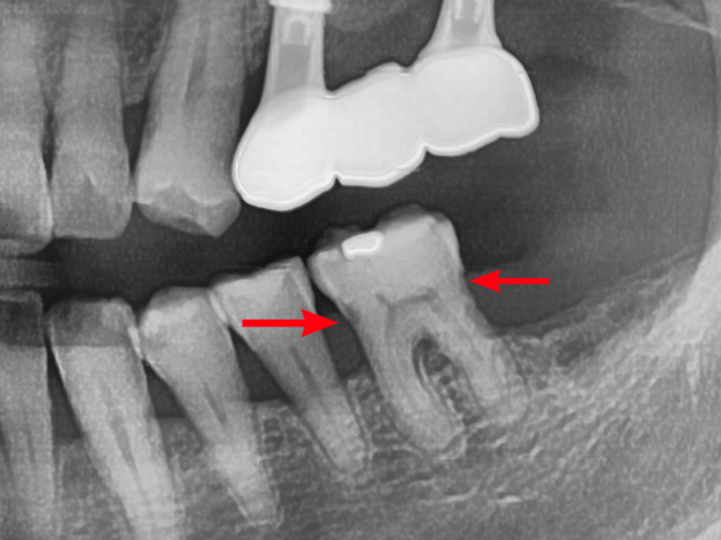

구강내사진과 엑스레이를 찍어보았는데요.

엑스레이 사진 양쪽 빨간 화살표 부분!!

치아 인접면 부분에 충치가 생긴것을 볼 수 있습니다.

치아 사이사이가 헐거워져 음식물이 자주 끼고,

그로 인해 인접면 충치가 생겼습니다.